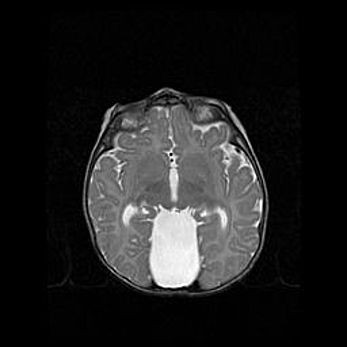

Аномалия Денди-Уокера. Признаки гипоплазии мозолистого тела.

Возраст: 5 месяцев 3 дня

Вес: 5550 г

Пол: мужской

Окружность головы: 39 см

Срок гестации: 40 недель

Аномалия Денди-Уокера – это порок развития головного мозга, для которого характерна триада симптомов: гипотрофия или аплазия червя мозжечка и/или полушарий мозжечка, расширение четвёртого желудочка с формированием ликворной кисты задней черепной ямки, гипертензионная гидроцефалия различной степени.

Гипоплазия мозолистого тела относится к дефектам внутриутробного этапа развития мозговой ткани, возникающим в процессе закладки структур головного мозга, что происходит на начальных этапах развития эмбриона.